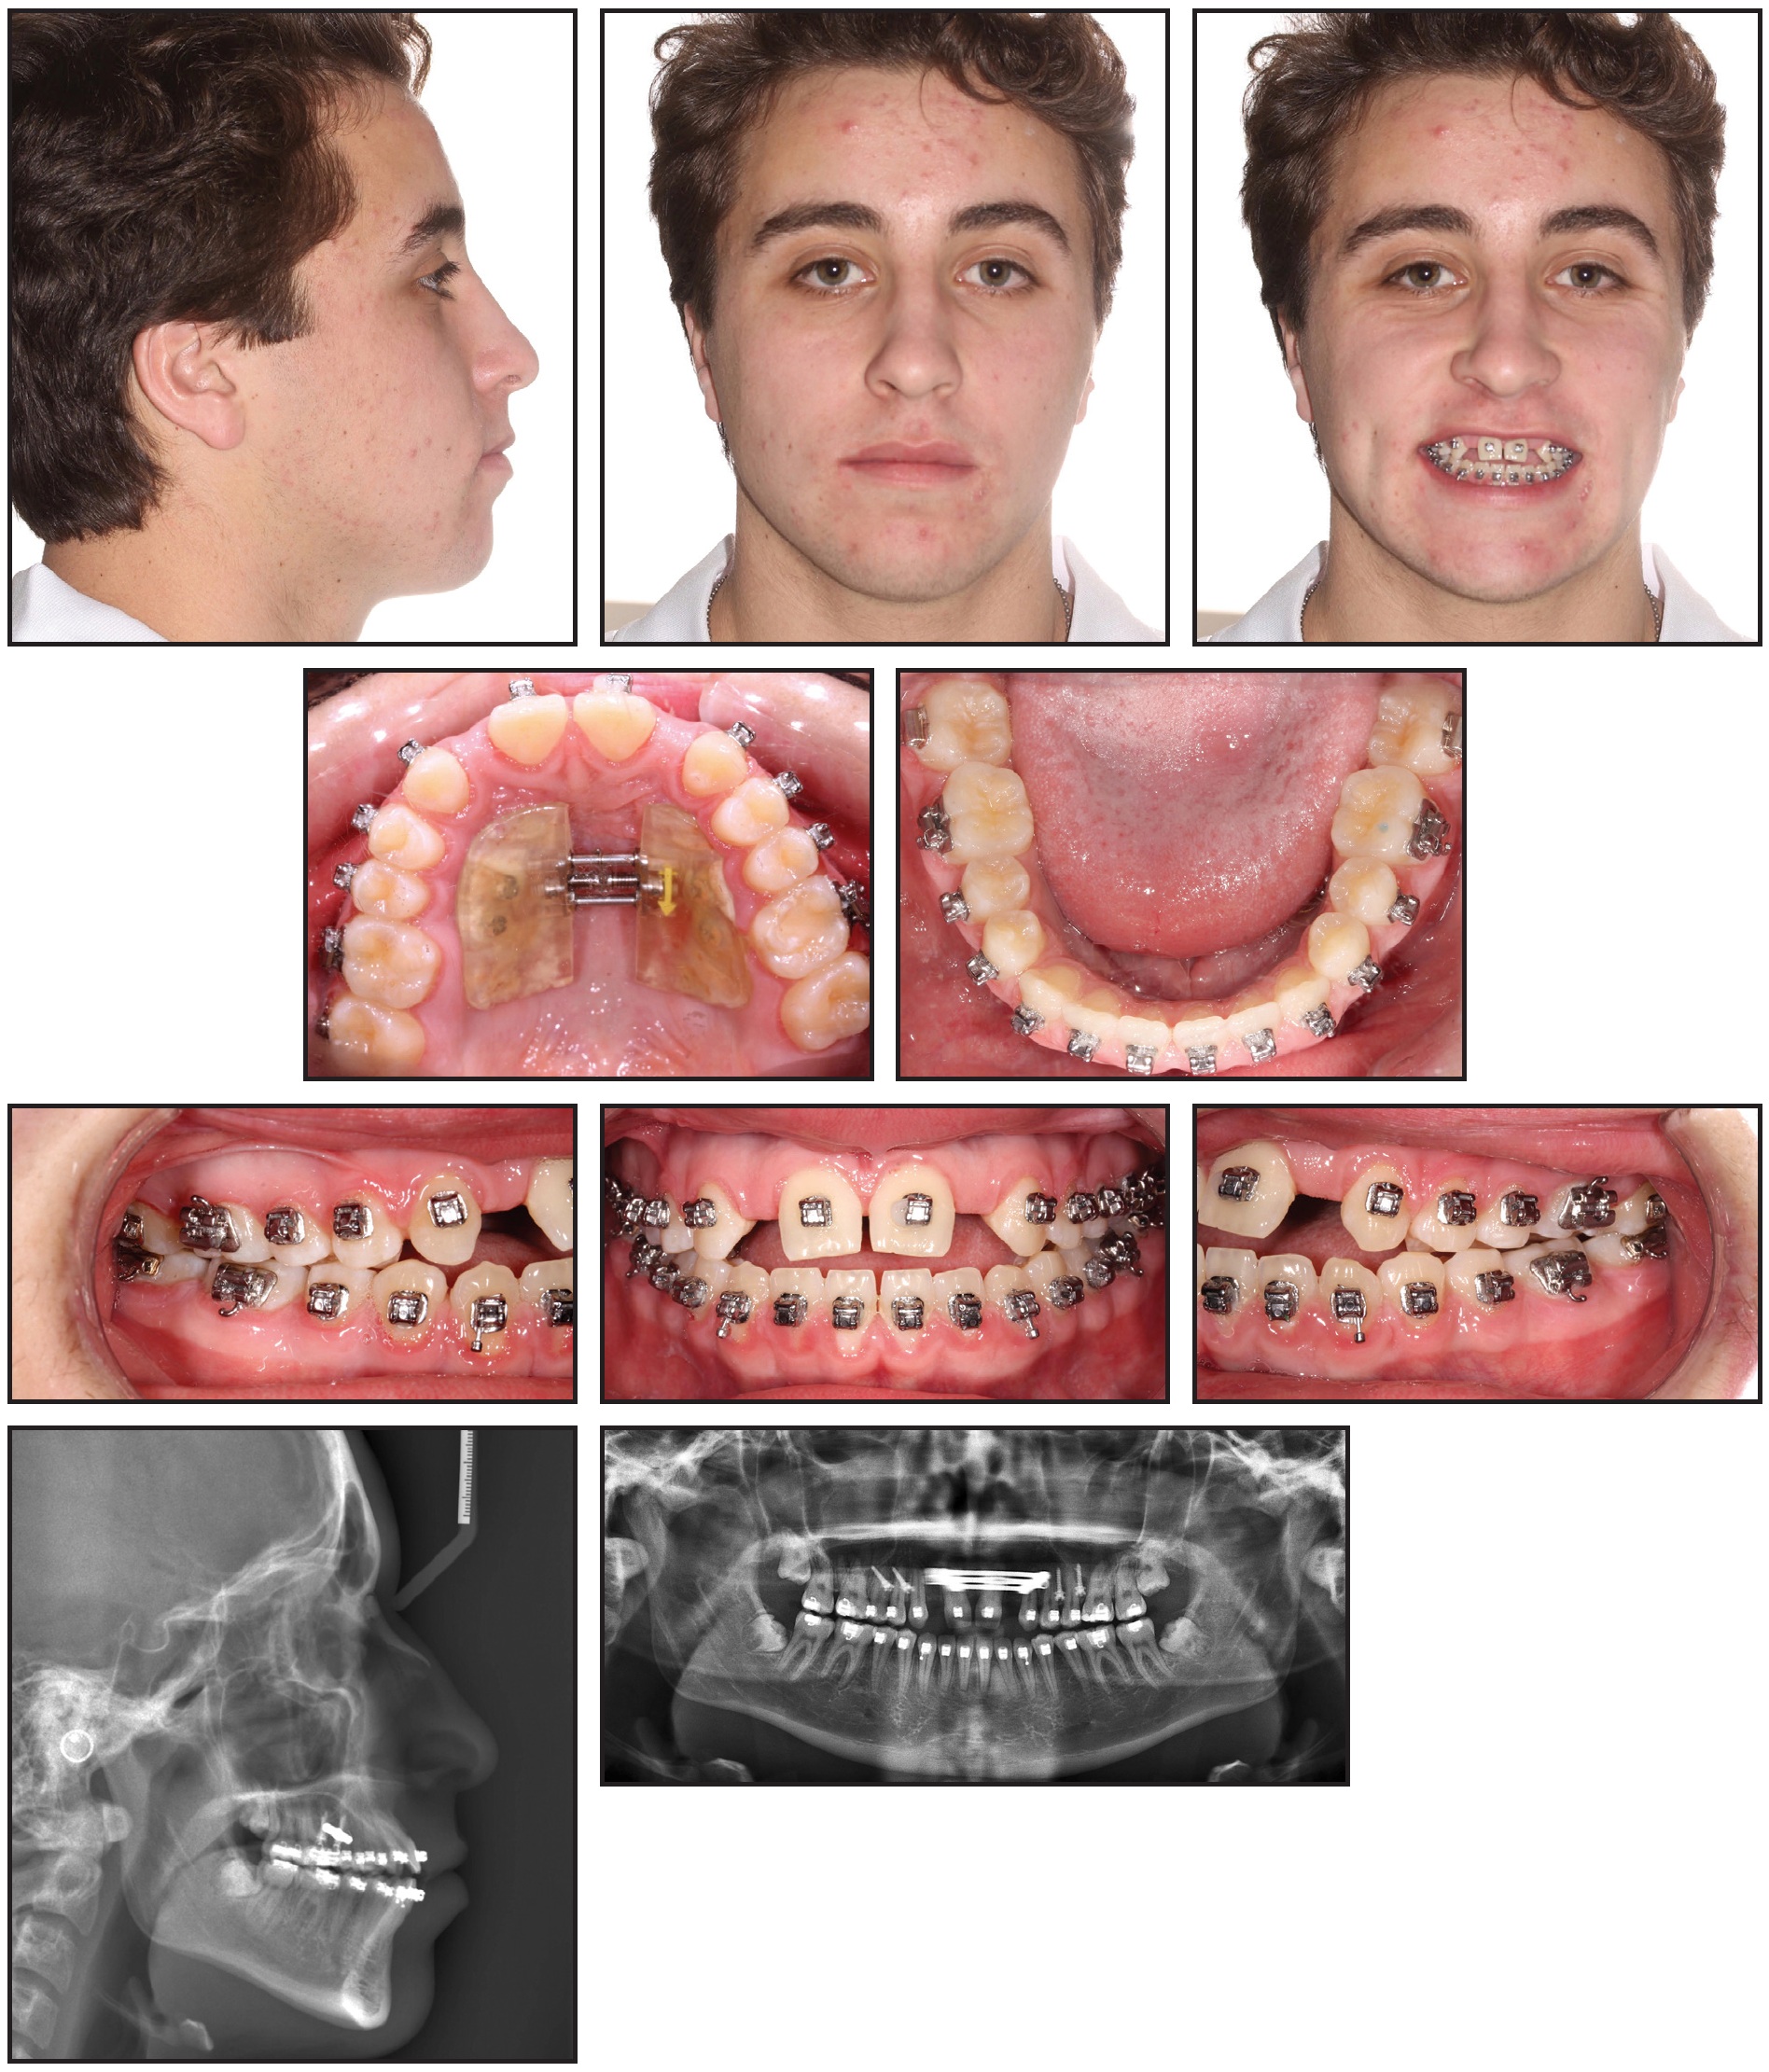

Four palatal mini-implants were placed by a periodontist in the maxillary premolar area, and the MARPE was cemented in place (Fig. 2).

Fig. 2 A. Four palatal mini-implants placed in upper premolar area. B. Expander cemented in place.

Since the patient was away at boarding school with no parental supervision, the expander was activated by a local orthodontist two or three times a week for about four months (Fig. 3A and 3B).

Fig. 3 Expansion completed after four months (continued in next image).

Fig. 3 (cont.) Expansion completed after four months.

The patient was then scanned for SureSmile custom archwires (Fig. 4).

Fig. 4 SureSmile** simulation.

Upper and lower .016" × .016" nickel titanium SureSmile archwires were inserted, with open-coil springs in the maxillary lateral incisor spaces. The expander and mini-implants were removed 10 months after placement.